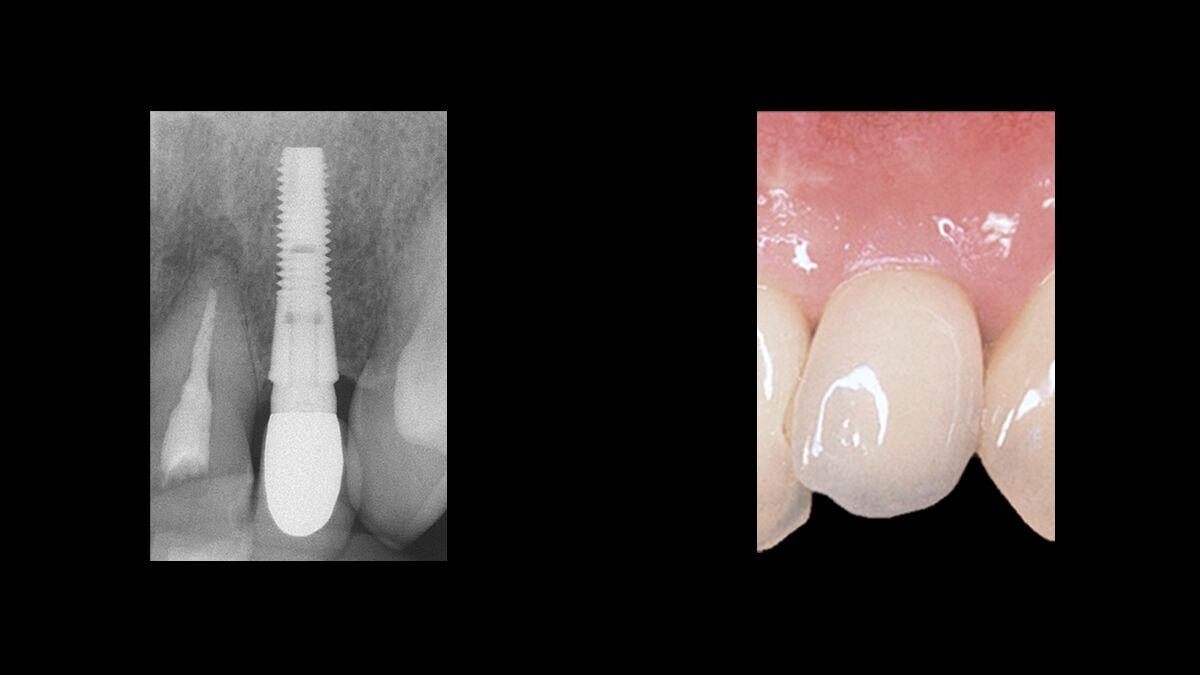

Uitstekende functie. Geweldige esthetiek.

Het behoud van marginaal bot is de basis voor het succes van een tandheelkundig implantaat en een belangrijke factor voor het esthetische resultaat.

Het ongeëvenaarde marginale botbehoud van Astra Tech Implant System EV zorgt voor: